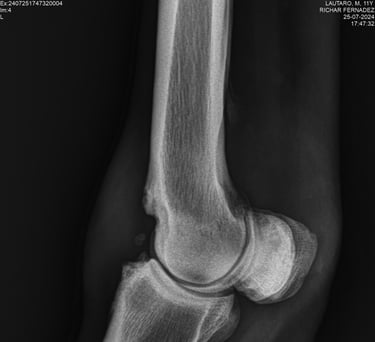

DIAGNOSTICO POR IMAGENES: ECOGRAFIA Y RADIOGRAFIA